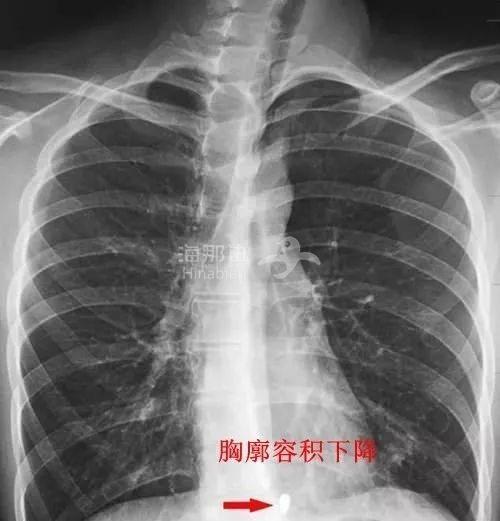

由于脊柱变形发生在胸腰段居多

颈椎前凸,胸椎后凸

还会导致胸廓旋转畸形和胸廓容积下降

损坏心肺功能以及累及脊髓

严重者会出现呼吸困难甚至行动迟缓的可能